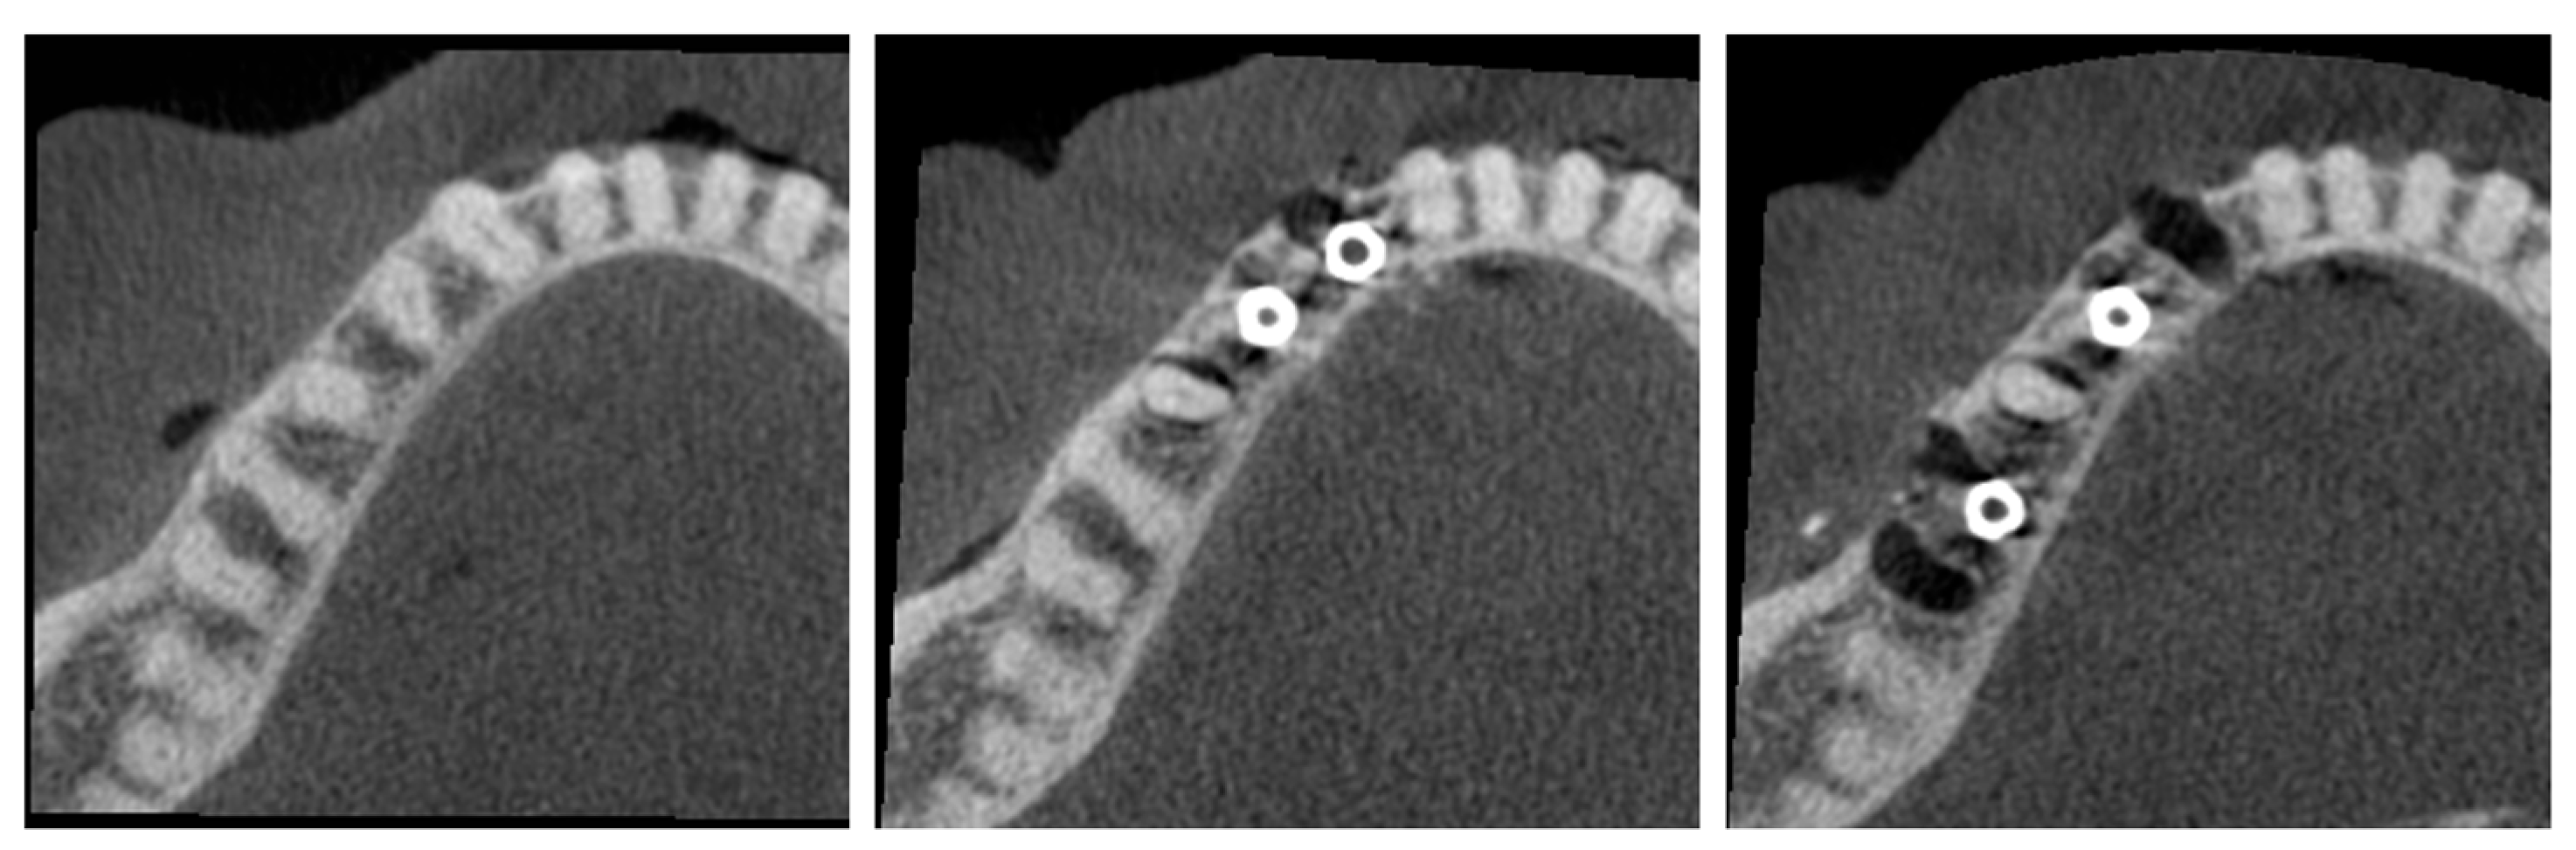

- C1—Configuration where two implants are side by side, that is, there are no teeth between the implants.

- C2—Configuration with a tooth between the implants.